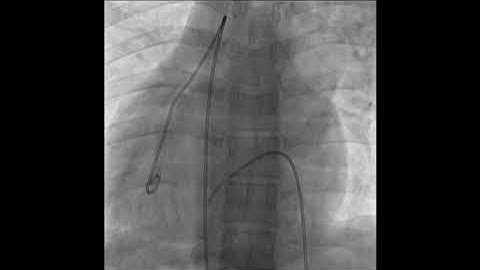

LV Angiogram Profiling Perimembranous VSD